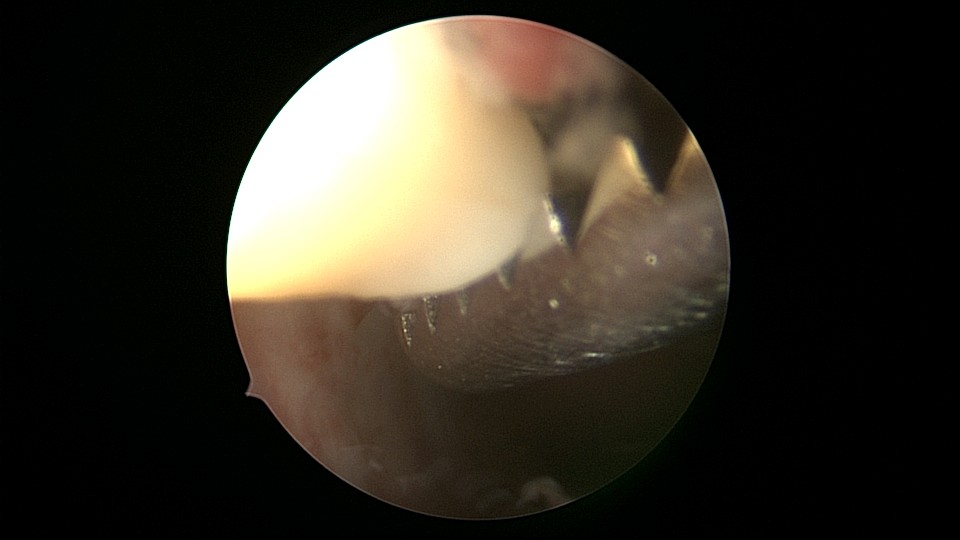

患者53岁,G3P1,剖宫产1次。安环13年,绝经8年,外院取环失败。患者阴道、宫颈及子宫萎缩,很难置入扩阴器,很难牵拉宫颈,宫颈外口位于前穹隆顶端,子宫极度前倾前屈位,且子宫与盆壁粘连,被拉长,宫腔镜很难进入,B超监护下异物钳扩张宫颈管上段及宫颈内口,宫腔镜艰难进入宫腔,见T型环两横臂嵌顿于两侧宫角,尾丝断裂,异物钳取出节育环,宫腔未见其他异常。